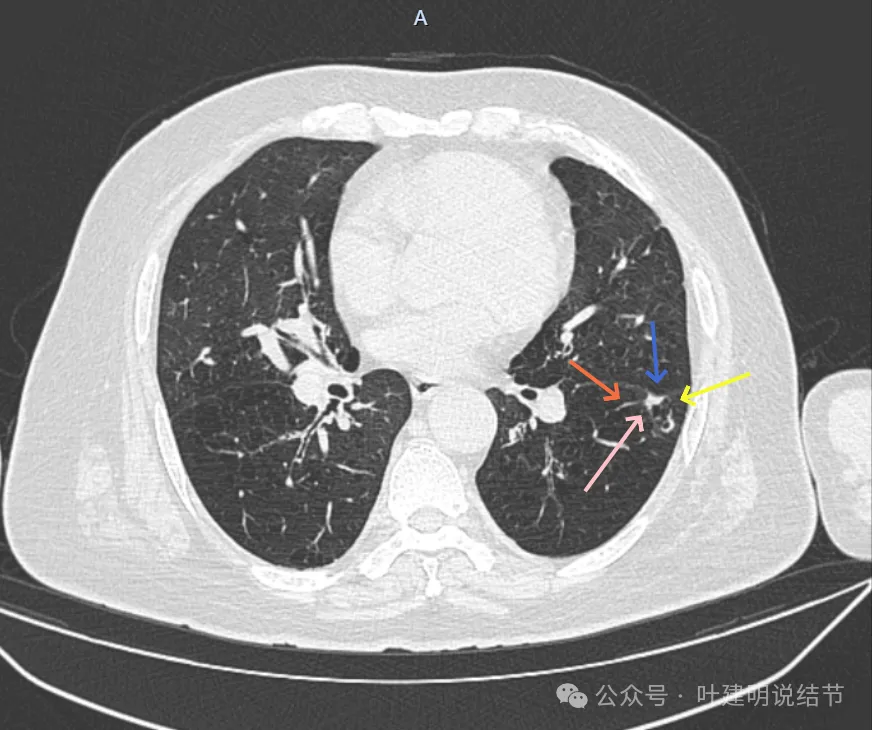

再看2024年9月时的影像:

病灶出现,紧贴叶间裂,有小血管走向病灶侧。

中间有空腔,叶裂侧实性并牵拉叶间裂。

囊腔灶、轮廓清、小血管进入囊壁、囊壁厚薄不均、叶间胸膜牵拉。

表面不平、混合密度、囊腔壁厚薄不均、内壁不光滑、有细支气管扩张通气征。

明显壁厚薄不均的囊腔灶,囊壁基本实性,表面不平,内壁不光滑,且邻近叶间裂并牵拉叶裂。

表面毛糙不平,部分区域有点像锯齿状。

表面不平细毛刺,中间空腔欠光滑、囊壁厚薄不均。

上图囊壁较厚,密度较高,轮廓与边界较清。

病灶边上也有多发小空泡样征,说明病灶有收缩力或对周围结构有影响。

上图显得像混合密度伴偏心空腔征。

上图是病灶边缘部位有血管走向病灶侧,并达病灶的地方有异常增粗。